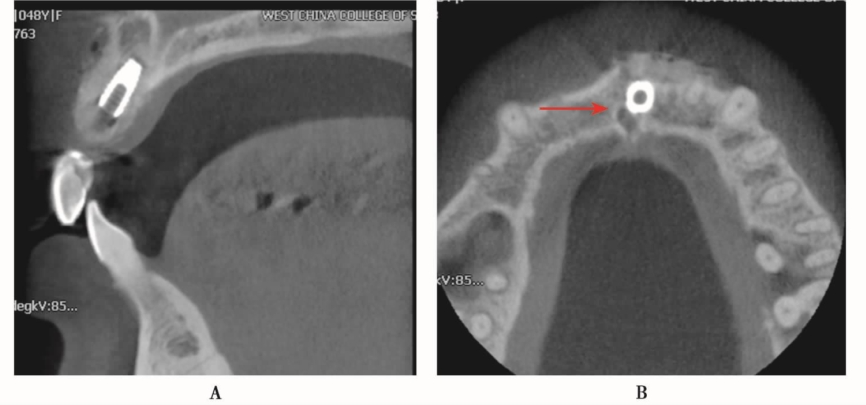

图1 CBCT显示种植体位于上颌窦内A.矢状位;B.水平位

种植体进入上颌窦以后,其位置和方向可以完全不一样,三维重建图像可清楚显示种植体的形状与邻近结构的相关关系(图2、图3)。